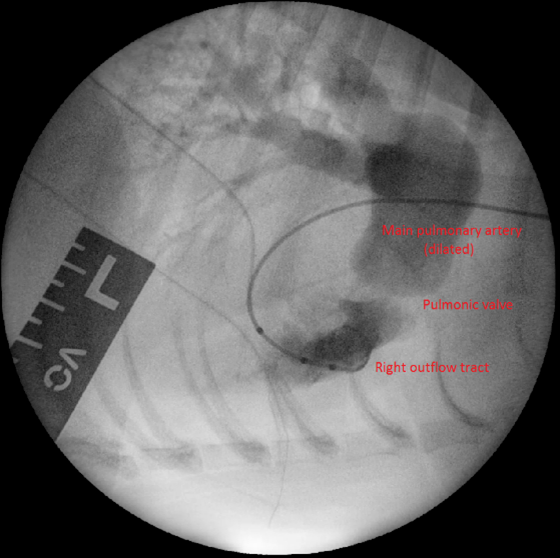

Surgical intervention is considered the treatment of choice for moderate to severe PS. Balloon valvuloplasty (BVP), a minimally invasive procedure, involves the insertion of a balloon catheter into the stenotic pulmonary valve and inflation to dilate the narrowed area (Figure 2). This technique has demonstrated excellent short- and long-term outcomes in dogs with valvular stenosis, with significant improvements in clinical signs and survival rates.

In cases where BVP is unlikely to be successful (such as in cases with mixed-type PS), pulmonary artery stenting may be pursued. This is a minimally invasive technique that involves the implantation of a metal stent across the stenotic lesion (Borgeat et al., 2021). Complications for this procedure, besides those listed for BVP, include stent fracture, migration and crimping.